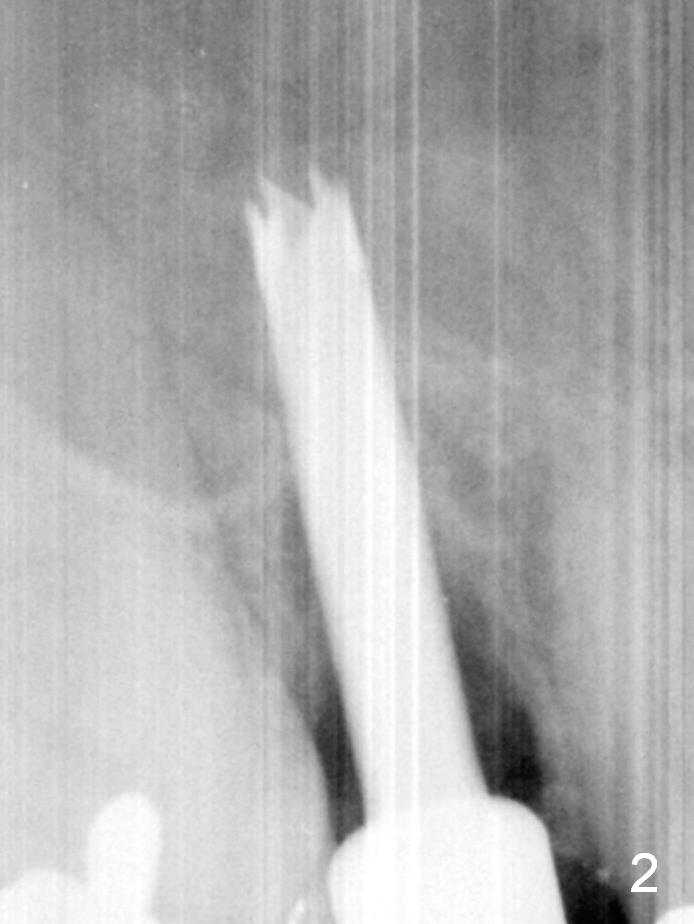

To prevent sinus lift related sinusitis, a shorter implant is going to be placed (Fig.1), approxi-mately 2 mm beyond the apex. Following extraction, the buccal plate (Fig.3a (coronal section): B) is not only ~ 2 mm shorter than the palatal one (P), but also thinner. Since the bone density of the palatal plate is higher, without osteotomy an implant is less likely placed in the middle of the socket (S (Fig.1); Fig.3b) than buccal (Fig.3c). Therefore drills are used to form osteotomy in the apical 1/3 of the palatal slope (Fig.3d (red arrow); SM: sinus membrane). When 3.3 mm Magic Drill (MD) is in place (Fig.2), the distal surface of the sinus septum is perforated without air leakage. Demineralized allograft (.0125-.085) is placed for sinus lift (Fig.4 *) prior to placement of 4.5x11 mm implant with ~ 30 Ncm. The implant is slightly buccal to the ideal position indicated in Fig.3e (curved blue line: sinus lift). A 4.5x4(2) mm pair abutment is placed for an immediate provisional to hold mineralized allograft in the remaining socket gaps (Fig.4 arrowheads, .5-1.5 mm). A 9 mm implant may avoid sinus floor perforation on the distal slope of the 2nd premolar. The osteotomy should have been established initially as mesial as possible. In fact the patient has nasal hemorrhage while sneezing for the first 2 days postop. Although he complains of pain buccal to the implant, the gingiva appears to heal 7 days postop (Fig.5). The distobuccal papilla appears to be displaced somewhat. Raising mucoperiosteal flap is most likely associated with postop pain and esthetic compromise. The implant appears to have osteointegrated 5 months postop (Fig.6). A 4.5 mmx15° 3 mm cuff angled abutment is placed for final restoration. The distolingual portion of the implant is supported by the regenerated bone 3 years post cementation (Fig.7,8).